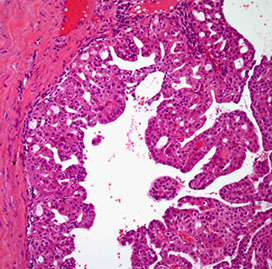

Mucinous cystic neoplasms (MCN)

Almost always in perimenopausal women

- tumor does not communicate with pancreatic ductal system (vs IPMN)

Gross: MC in pancreatic tail c multiloculated cysts filled c mucin

Micro: lined by tall, simple cuboidal epithelium on top of a stroma so dense it looks like ovary

- smear is hypocellular, has thick mucous and columnar cells and is CEA (+)

- if cell lining is very atypical or glands are invading into capsule or beyond, dx is mucinous cystadenocarcinoma

- can see gastric foveolar, pseudopyloric, small and large intestine-type epithelium

- can grade dysplasia as low, medium, or high

IHC: (+) SMA/inhibin /ER/PR in ovarian stroma, cytoplasmic PAS, CEA/EMA and CK 19/7/8/18 in epithelial cells

Genes: mutated p53 and RNF43 tumor suppressor genes and KRAS oncogene, also SMAD4/DPC4

Tx: Excision is sufficient, except for those found to have carcinoma

Px: ~1/3 have invasive carcinoma (mucinous cystadenocarcinoma), thus it is of utmost importance to remove ASAP

- 1/2 of pts c carcinoma die from the tumor; usually mets are local to peritoneum or ovary

Benign MCN

MCN